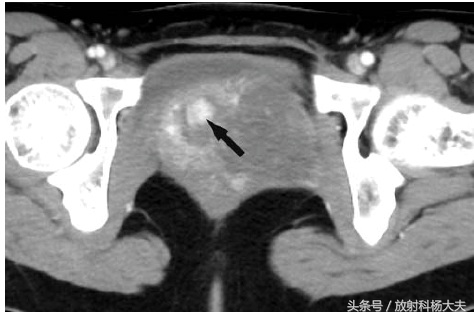

这个女性盆腔的核磁,有几个要点:T2WI上高信号,可见到一些旋涡样改变,增强扫描延迟强化明显。提示,有粘液成分,有血供。结合病人年龄和部位,这是一个侵袭性血管粘液瘤。

AAM在CT中表现为瘤体密度与正常肌肉对比呈略低密度或等密度,增强扫描时瘤体明显强化,并呈漩涡状改变,且动态增强扫描显示瘤体不均匀缓慢强化,延迟期也明显强化;MRI表现为瘤体在T1加权像上呈低信号或等强度,瘤体在T2加权像上呈高信号或等信号,MRI也可以显示瘤体呈漩涡状改变。